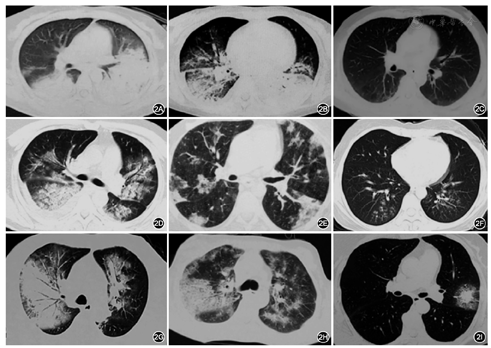

特发性间质性肺炎包括特发性肺纤维化(IPF)、非特异性间质性肺炎(NSIP)、隐源性机化性肺炎(COP)、呼吸性细支气管炎伴间质性肺炎(RB-ILD)、脱屑性间质性肺炎(DIP)和急性间质性肺炎(AIP)[10]。其中,NSIP、COP和AIP和此次新冠肺炎影像特征多有相似之处,并可表现为急性过程(图3A,图3B,图3C,图3D,图3E,图3F)。(1)NSIP的常见影像表现为双肺弥漫的GGO、网格影,伴或不伴牵张性支气管扩张。病变沿支气管血管束分布或者胸膜下分布(图3A、图3B、图3C)。(2)机化性肺炎典型影像表现为沿支气管血管束或胸膜下分布的实变影,可伴有GGO(图3D、图3F)。(3)AIP容易快速进展为呼吸衰竭和急性呼吸窘迫综合征、其病理基础是弥漫性肺损伤(DAD)。影像表现为双肺弥漫的实变和磨玻璃影(图3E)。

NSIP、机化性肺炎或者AIP可以是特发性,也可以继发于结缔组织病(CTD)、过敏性肺炎或者药物性肺损伤[11,12,13]。CTD相关肺损伤从临床、影像、病理都可以与新冠肺炎有相似表现。比如皮肌炎相关间质性肺疾病(ILD),患者临床可表现为中低度发热、咳嗽、呼吸困难和乏力,实验室检查可以有CK、LDH增高,胸部CT可以表现为多种类型的间质性肺炎。

与新冠肺炎鉴别:(1)病程:新冠肺炎多数在起病1~2周出现呼吸困难,比多数的CTD-ILD要快。因此如果患者在2~4周后加重,新冠肺炎的概率比较低。(2)全身情况:皮疹、关节痛等肺外表现有助于诊断CTD-ILD。(3)影像学表现:新冠肺炎仍然是以GGO或实变为主要表现,网格、索条影相对较轻。如果以网格索条为主、而GGO或实变较少或者缺如,甚至出现蜂窝肺,则提示其他原因所致的间质性肺炎。(4)病原学检测:咽拭子核酸检测及外周血新冠病毒IgM抗体检测有助于诊断。自身抗体检测阳性有助于诊断CTD-ILD。